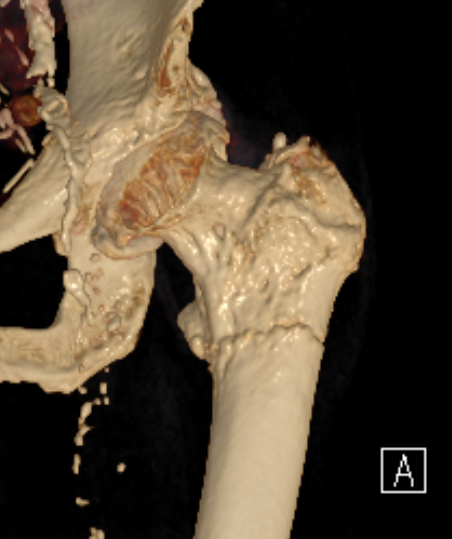

Atypical femur fracture xrayAtypical femur fracture CTAtypical femur fracture CT 2

Lateral beaking subtrochanteric region

2. Lower limb alignment

- associated with bilateral AFFs

- head neck varus

- lateral femoral bowing

- be careful of bowed femurs in Asian women